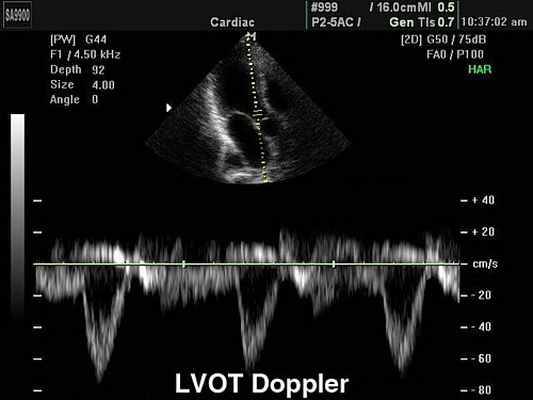

Эходопплеркардиография — это инструментальный метод исследования сердца и кровеносных сосудов, при котором применяются ультразвуковые технологии. Как и при «рутинных» (М-режимной и двухмерной) эхокардиографиях (ЭхоКГ), данная методика использует высокочастотные звуковые волны, чтобы создать изображение сердца. Но помимо этого, чтобы определить скорость и направление кровотока, она дополняется эффектом Допплера.

Допплерометрия демонстрирует при этой патологии повышенную скорость кровотока (признак сужения) и может быть использована для оценки «эффективной площади отверстия» (степени выраженности стеноза).

Преимущества и недостатки допплерометрии сердца

ЭхоКГ способна определить направление кровотока, измерить скорость движения крови и сердечной стенки, если она дополняется эффектом Доплера. Одним из недостатков эхокардиографии с допплеровским анализом является то, что для получения точных результатов ультразвуковой луч и поток крови должны быть максимально параллельны, что ограничивает возможность исследовать некоторые отделы сердца.

Измерение скоростных характеристик позволяет оценить: